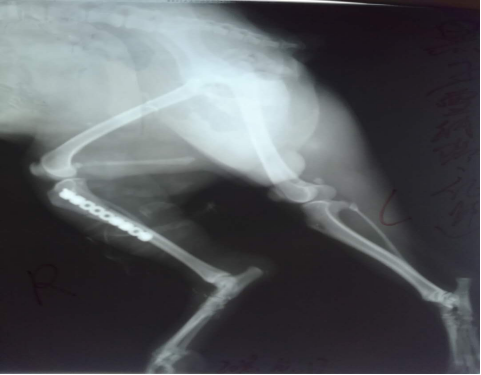

雪納瑞大黑被車撞到,導致右后腿無法站立,X光檢查脛骨骨折,在別的醫院拍完X光后轉到我院進行手術,經過精心手術成功斷端成功對接,剩下的只需要主人的精心呵護***痊愈。也提醒廣大寵物主人一定要看好自己的寵物,不要亂跑以防出現事故。